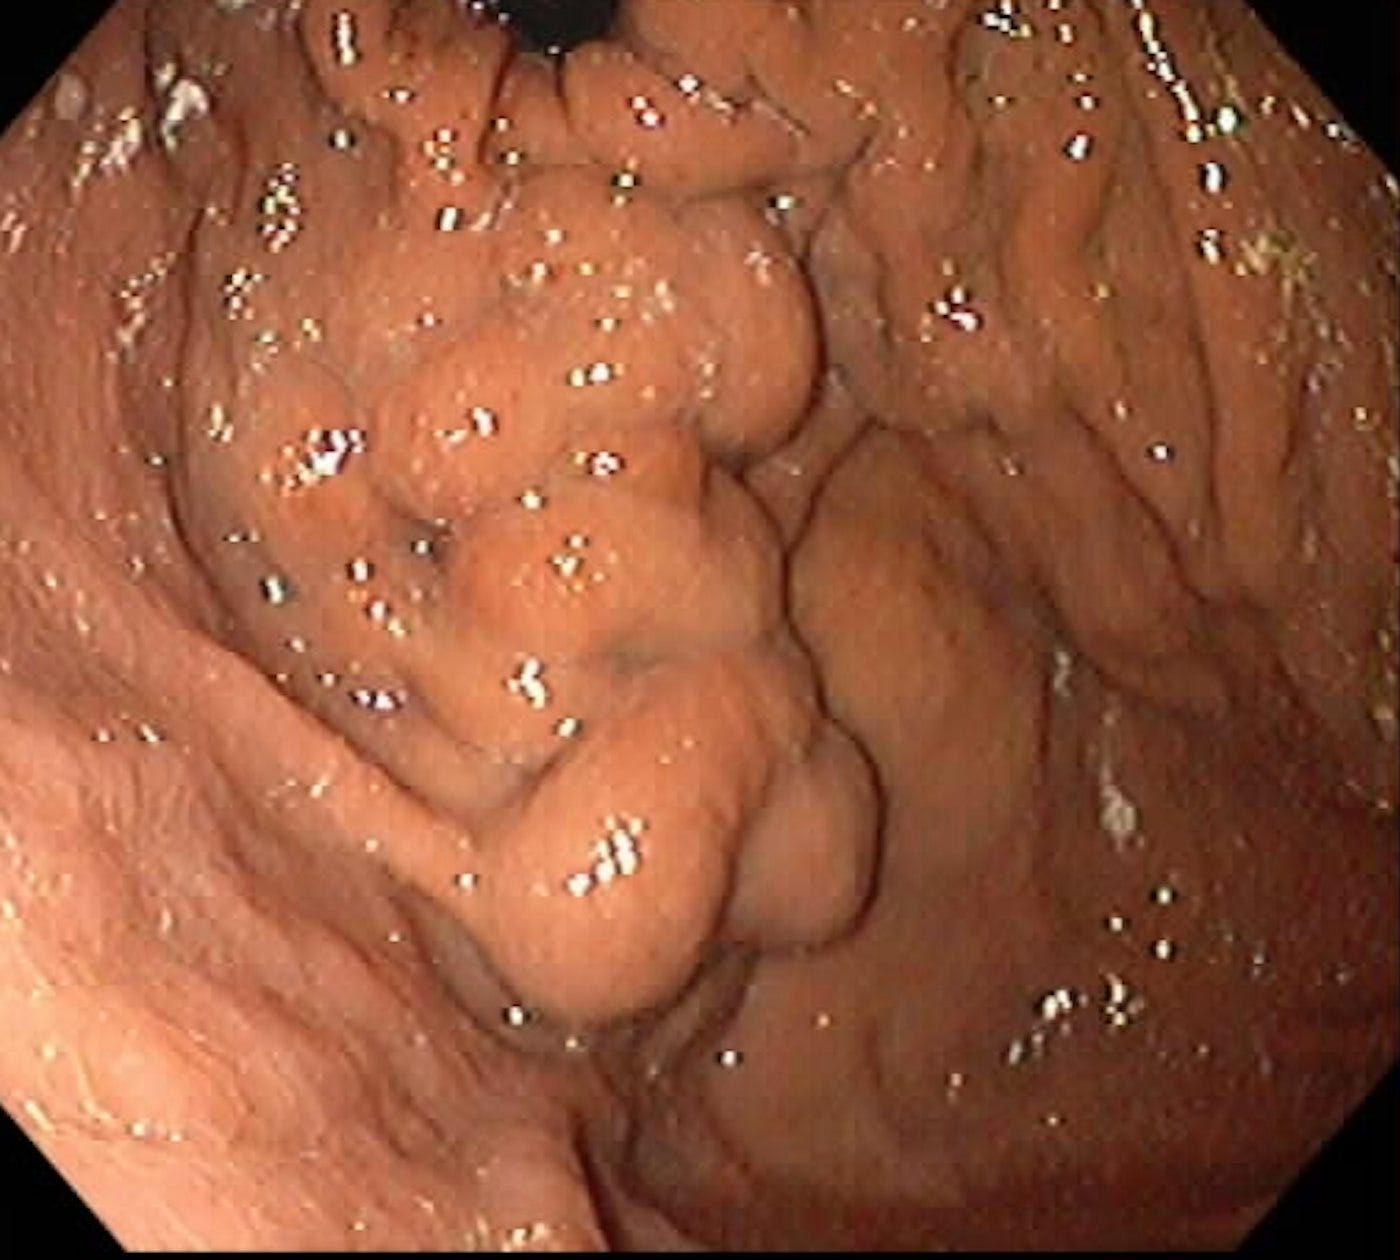

What Type of Varices Are These According to the Sarin Classification?Aug 05, 2025114ShareLeave a commentSarin Classifications, Ref.: Henry Et Al. Cgh 2021AnswerThis is the esophagus. Thus, the patient had esophageal and varices extending into the greater curvature of the stomach, GOV2 based on the Sarin classification.SharePreviousNext

GOV2